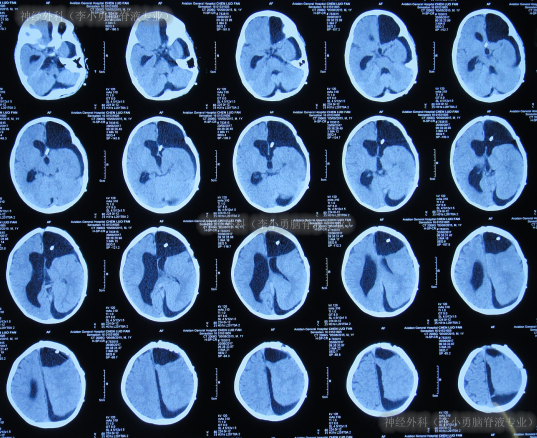

但出院后仅半月时间内,出现了不断加重的左侧肢体轻瘫,口角右斜,头向左斜和走路不稳的症状,出院后18天即2017年4月24日,当地医院查头颅CT硬膜下积液、脑积水加重(图-6)。

图-6:2017年4月24日头颅CT

入院后4天即2017年4月28日,进行了第1次手术:硬膜下积液引流术。术后3天即2017年4月30日,查头颅CT示硬膜下积液引流术后,脑室有所缩小(图-7)。

图-7:2017年4月30日头颅CT

硬膜下积液引流术后6天即2017年5月3日,患者症状仍未改善,查头颅核磁(图-8)后脑积水反而变更多,认为有“囊肿”。

图-8:2017年5月3日头颅核磁增强

第2次手术:软性神经内镜脑室内检查术和脑内囊肿造瘘术后第2天(2017年5月6日)和第3天(2017年5月7日)两次查头颅CT(图-9)均示脑室仍未缩小,反进一步扩张。

图-9:2次查头颅CT

第2次手术软性神经内镜脑室内检查术和脑内囊肿造瘘术后10天即2017年5月14日,进行了第3次手术:脑室腹壁外引流术;术后当天查头颅CT后认为脑室有缩小(图-10)。

图-10:2017年5月14日头颅CT